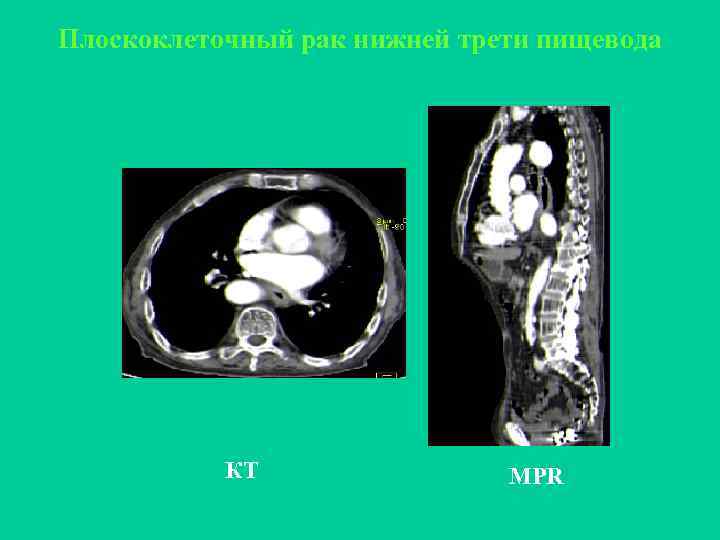

Плоскоклеточный рак нижней трети пищевода КТ MPR